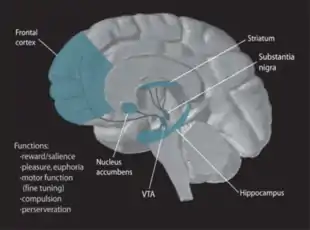

Dopamine

Dopamine, a neurotransmitter, has been linked with feeding behaviors. In an experiment, scientists measured how much food and water mice consumed when they were born without dopamine in their systems. They found that without dopamine, the mice would starve and be dehydrated to the point of death. The scientists then injected the mice without dopamine with its precursor, L-DOPA, and the mice started eating again. But, even though the mice were born without dopamine in their systems, they still had the capacity to control their feeding and drinking behaviors, suggesting that dopamine does not play a role in developing those neural circuits. Instead, dopamine is more closely related to the drive for hunger and thirst. Although the lack of dopamine resulted in adipsia in these rats, low levels of dopamine do not necessarily cause adipsia. [9]

Other findings in support of the role of dopamine in thirst regulation involved the nigrostriatal pathway. After completely degenerating the pathway, the animal becomes adipsic, aphagic, and loses its interest in exploring. Although dopamine plays a role in adipsia, there is no research involving exclusively the relationship between adipsia and dopamine, as changes in dopamine simultaneously mediate changes in eating and curiosity, in addition to thirst.[10]